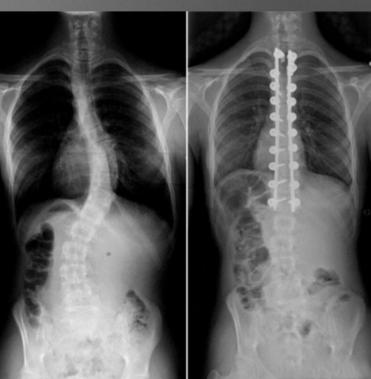

脊柱侧弯是指脊柱偏离纵向轴线,形成异常侧向曲线异常,曲线存在于三个维度,而非一个平面。

✎早期(侧弯角度小)物理治疗:运动治疗

矫形支具(影响活动)

✎后期(侧弯角度大)治疗:外科手术(并发症多)